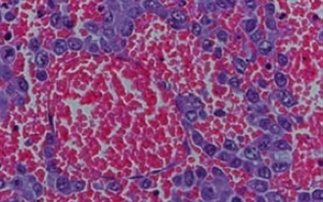

Ο παθολόγος Μπεν Κόουελ, από την Υπηρεσία Λοιμωδών Ασθενειών, δήλωσε ότι οι περιπτώσεις καρκίνου του ήπατος θα διπλασιαστούν εντός της δεκαετίας στην Αυστραλία, φτάνοντας τις 2.500, αν δεν γίνει κάτι άμεσα για να αντιμετωπιστούν τα αίτια.

Ο ίδιος δήλωσε επίσης ότι η ηπατίτιδα Β και C αποτελούν τα κύρια αίτια του καρκίνου του ήπατος -μετά το κάπνισμα- σε παγκόσμια κλίμακα.

Όπως αναφέρει το ΑΠΕ-ΜΠΕ, η ηπατίτιδα Β έχει προσβάλει περίπου 200.000 άτομα στην Αυστραλία, κυρίως Αβοριγίνες ή γεννημένους εκτός Αυστραλίας, ενώ η ηπατίτιδα C 280.000 Αυστραλούς, προκαλείται δε κυρίως από χρήστες ναρκωτικών που χρησιμοποιούν κοινές σύριγγες.

O δρ Κόουελ, ο οποίος παίρνει μέρος σε Συνέδριο που γίνεται στη Νέα Ζηλανδία, πρόκειται να κάνει έκκληση στις κυβερνήσεις και σε υπηρεσίες υγείας, να δεσμευτούν να εντατικοποιήσουν τις προσπάθειές τους για την έγκαιρη εντόπιση και θεραπεία της ηπατίτιδας προκειμένου να σωθούν χιλιάδες ζωές.

«Απαιτείται μια δραστική αναβάθμιση μέσων και προσπαθειών προκειμένου να σταματήσει η επιδημία στα πρώτα της στάδια, διαφορετικά ο καρκίνος του ήπατος θα αποβεί ο υπ’ αριθμόν 1 θανατηφόρος καρκίνος στην Αυστραλία και Ν. Ζηλανδία» είπε ο διακεκριμένος επιστήμονας.